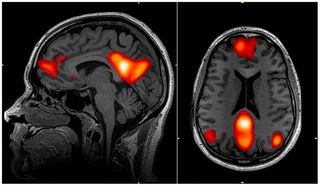

A study published in the journal Cognitive, Affective, & Behavioral Neuroscience found that long-term meditation practitioners exhibited decreased activity in the default mode network (DMN), the network of brain regions associated with mind-wandering and self-referential thinking. Excessive activity in the DMN is associated with a noisy (mind-chatter) and restless mind. Researchers note that the DMN has been found to be most highly active when individuals are left to think to themselves undisturbed or during tasks involving self-related processing, and less active during tasks requiring cognitive effort. Experienced meditators thus exhibit decreased DMN activity during meditation (and even during resting states), as a result of their conditioned focus, demonstrating a reduced tendency self-referential thinking and mind wandering.

Quieting the mind through mindfulness and meditation has also been shown to impact the brain’s neuroplasticity, the ability of the nervous system to change its activity in response to intrinsic or extrinsic stimuli by reorganizing its structure, functions, or connections. Studies on meditation have shown that regular practice can enhance cortical thickness and increase gray matter density in brain regions involved in attention, interoception (the ability to sense your body’s internal environment), and sensory processing, leading to enhanced cognition, memory capacity, and general intelligence.

More gray matter is associated with better cognitive function, while decreases in gray matter are associated with Alzheimer’s disease and other related dementias”